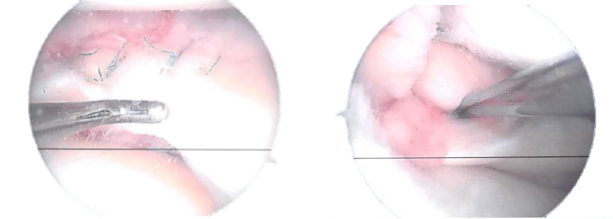

A grade 1 to grade 2 median condylar osteochondral lesion of the femur was also found. The ACL had some fraying and degeneration. the healing of the medial meniscus. Sutures from Fast-Fix were used. The peripheral laceration from the posterior horn to the mid body was repaired with seven sutures.

Actual Arthroscopic images taken during the operation